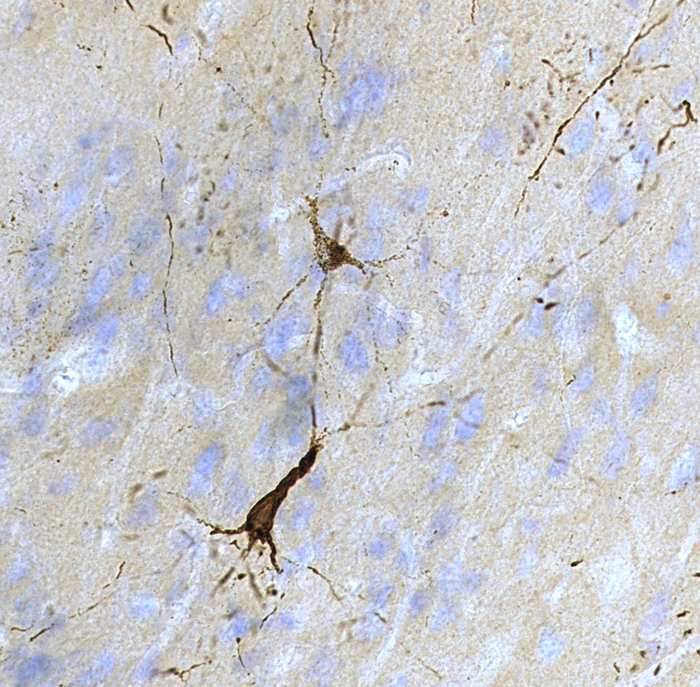

To look for signs of TBI damage, the researchers then cut the brains into thin slices and treated the slices with antibodies made to detect phosphorylated tau proteins found in humans or mice. This form of tau is a hallmark of damage that is often seen in the brains of Alzheimer’s disease patients, or in people who have suffered TBIs, including chronic traumatic encephalopathy (CTE).

When they looked at the brains under a microscope, they saw that one of the antibodies stained muskoxen brains at easily detectable levels, whereas the bighorn sheep brains had lightly detectable levels of staining by a different antibody.

Further analysis supported the idea. For example, the prefrontal cortex of the muskoxen brains had high levels of tau protein tangles, especially near the surface of the cortex.

“This pattern is sometimes seen in the brains of people who suffer from CTE,” Dr. Ackermans said. “Our results open the possibility that these animal’s brains undergo chronic, repetitive damage, as seen in some TBI patients.”